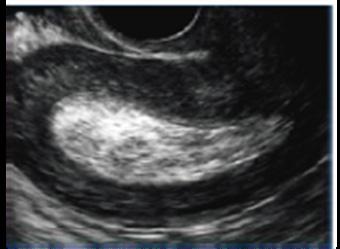

Certeza: La ecografía transvaginal es la prueba confirmatoria de embarazo. A las 4.5 semanas, se observa saco gestacional; a las 5 semanas, se encuentra embrión, y a las 6 semanas es posible auscultar los latidos cardiacos fetales con el doppler . También se considera la percepción de movimientos fetales por parte del médico.

Figura 11. Ecografía de I trimestre Examen de certeza para confirmar un embarazo eutópico y viable